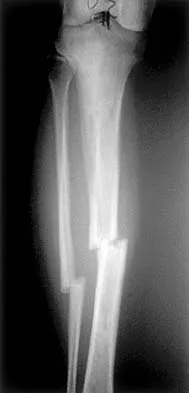

Figures 7a and 7b show the radiographs of a 51-year-old woman who injured her left leg after falling off a stepladder. Surgical reconstruction is performed with a compression screw and side plate; the postoperative radiograph is shown in Figure 7c. Following gradual progression of weight bearing, she reports that she slipped again and placed full weight on the extremity. She now notes a new onset of increased pain in her left thigh and hip region. Follow-up radiographs are shown in Figures 7d and 7e. Reconstruction should consist of

The initial fracture was an unstable reverse oblique intertrochanteric fracture with subtrochanteric extension. Initial fixation with a high-angled screw and side plate construct may not provide stability as well as a 95 degree fixed-angle device or a intramedullary hip screw device. The follow-up radiographs show loss of fixation and further propagation of the fracture distally. Reconstruction would best be accomplished with hardware removal and conversion to a long intramedullary nail with femoral head fixation or a 95 degree angled plate and screw device. Conversion to a longer plate does not improve the biomechanical situation at the primary fracture site. In situ bone grafting would not provide any additional stability and would not correct the deformity. The proximal femoral fracture is not amenable to retrograde nailing. Cerclage wiring will not sufficiently enhance stability and is not indicated. Bridle SH, Patel AD, Bircher M, Calvert PT: Fixation of intertrochanteric fractures of the femur: A randomized prospective comparison of a gamma nail and dynamic hip screw. J Bone Joint Surg Br 1991;73:330-334. DeLee JC: Fractures and dislocations of the hip, in Rockwood CA Jr, Green DP, Bucholz RW, Heckman JD (eds): Rockwood and Green's Fractures in Adults, ed 4. Philadelphia, PA, Lippincott-Raven, 1996, pp 1659-1825. Haidukewych GJ, Israel TA, Berry DJ: Reverse obliquity fractures of the intertrochanteric region of the femur. J Bone Joint Surg Am 2001;83:643-650.